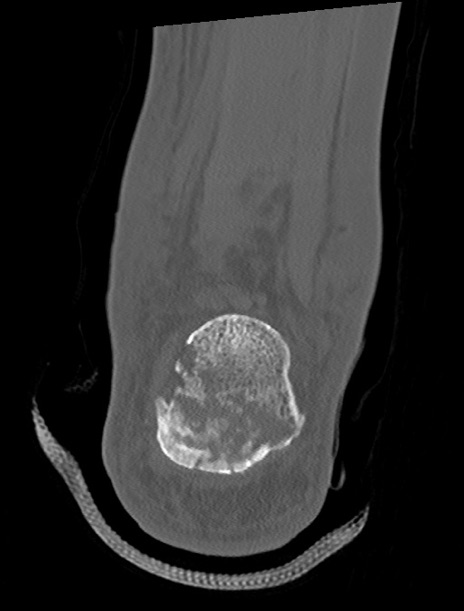

症例37 左足関節CT(冠状断像)

左足関節CT

矢状断像